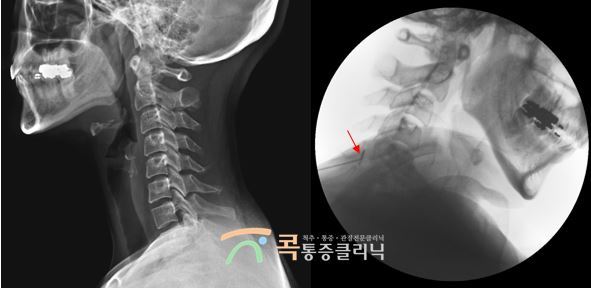

잦은 두통 대표 원인 4 경추성두통

고개를 숙일 때 심한 통증이 있고 심한 어깨, 목 통증이 두통과 함께 있다면 경추에 원인이 있을 수 있습니다. 초기에는 일반 두통약이나 진통제를 복용하면 통증이 완화되지만 점점 두통이 잦아지고 통증이 악화됩니다. 경추성두통은 대표적인 2차성두통으로 목디스크, 일자목, 거북목, 목 주변 신경, 관절, 인대 이상으로 발생합니다. 두통의 복합적인 원인을 세심하게 판독하여 정확한 진단이 선행되어야 하며 병변 부위를 치료하면 두통은 자연스럽게 호전됩니다.